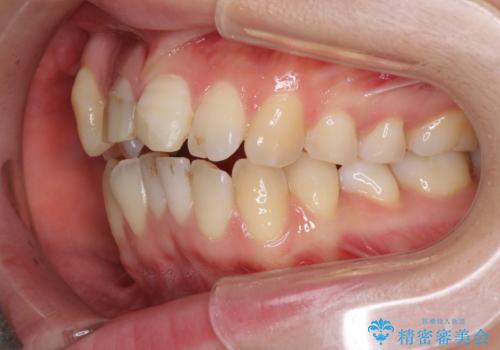

補助装置により上顎歯列を遠心移動させたため、非抜歯でしたが口元の突出感をある程度改善させることができました。

欠けてしまった前歯もオールセラミッククラウンにて自然に補綴することができました。